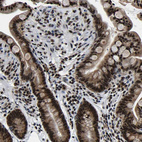

Immunohistochemical staining of human cerebral cortex, gastrointestinal, kidney and lymphoid tissues using Anti-LUC7L3 antibody HPA018475 (A) shows similar protein distribution across tissues to independent antibody HPA018484 (B).